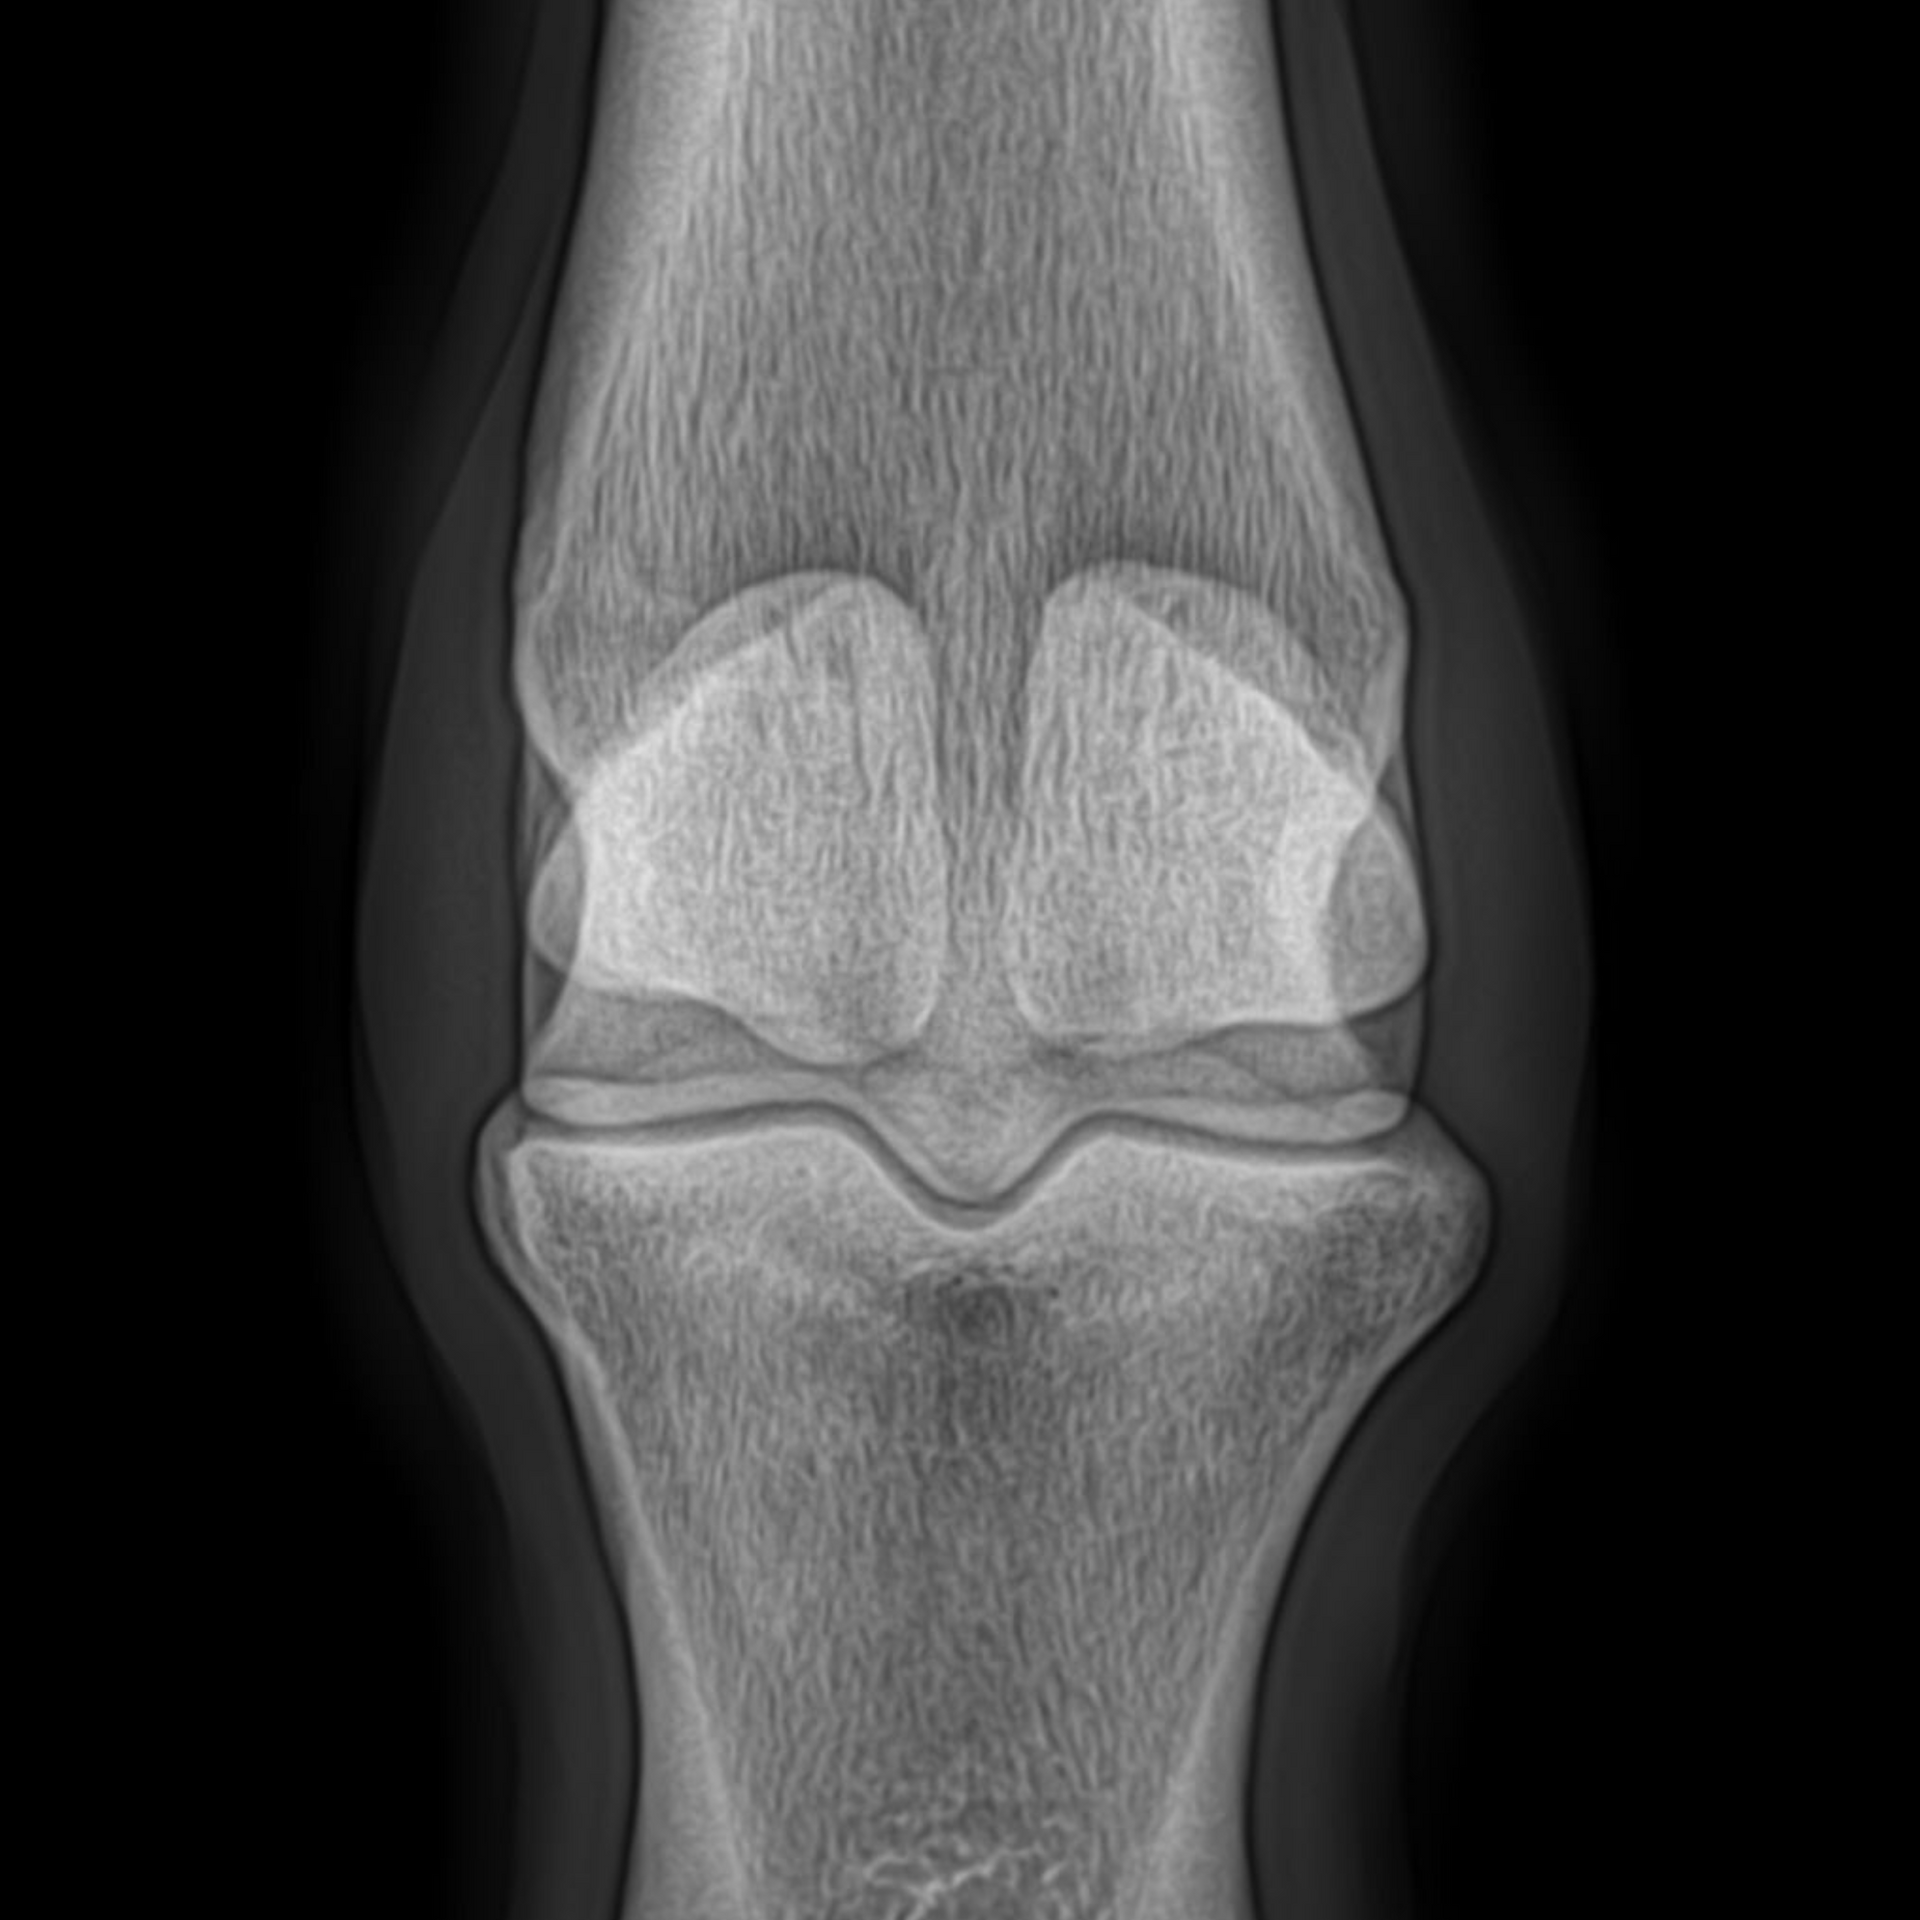

Met een röntgenologische keuring brengen we het skelet in beeld. Hiermee verkrijgen we een overzicht van eventuele OC(D), cystes, artrose, kissing spines, et cetera. Dankzij extra zware kwaliteit röntgenapparatuur, kunnen ook goede foto's van hals en rug worden genomen.